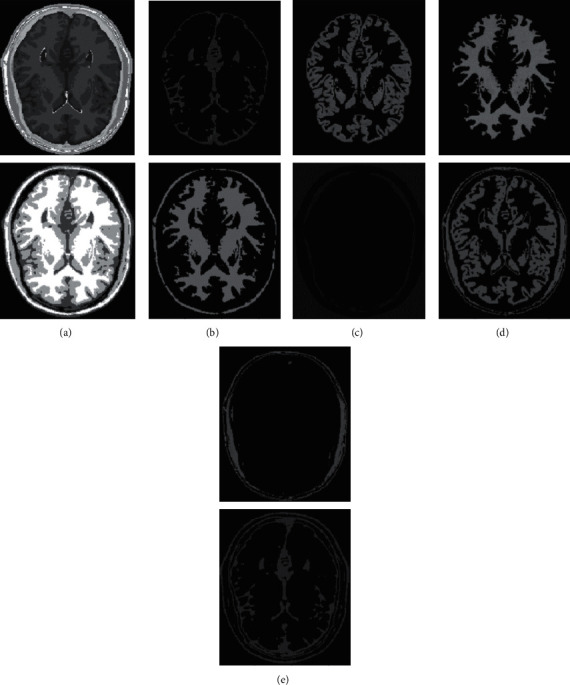

Figure 5.

Comparison of clustering results of different algorithms for Figure 8.

In human brain magnetic resonance scans, there are many structural tissues that do not belong to the brain, such as fat, the skull, muscle, and other tissues. Because the gray information of these tissues and the gray information of particular brain structures are so highly comparable to one another, proper segmentation of brain tissues is made more difficult as a result. Therefore, when segmenting brain tissue, it is required to exclude the tissues that do not belong to the brain in order to assure the correctness of the segmentation. This is done to ensure the correctness of the segmentation. Nevertheless, the procedure of removing tissue that is not part of the brain is challenging and complicated. In this study, the nonbrain tissues have been grouped together under the same category or cluster. Figures 4 and 5 show the segmentation results, which show that the segmentation results of the K-means clustering algorithm have a lot of noise, the segmentation results of the FCM algorithm contain a small amount of noise in white matter and cerebrospinal fluid, and the segmentation results of the hierarchical cluster algorithm remove the noise, but the cerebrospinal fluid in the brain sulcus is also smoothed out. These results can be seen by looking at the segmentation. On the other hand, the results of the mean-shift algorithm's segmentation are the most accurate of all of them. Despite the fact that Figures 4 and 5 demonstrate the results of segmentation using different methods, they are unable to portray the results of distinct tissues in a way that is intuitive. As a result, the experiment provides evidence of the segmentation outcomes of several categories. The benchmark of several different types of tissues in the selected image is shown in the first row of Figures 6–11. The remaining rows of the figure contain the clustering results corresponding to K-means clustering, fuzzy c-means clustering, maximum entropy clustering, Gaussian mixture model, mean-shift, and hierarchical cluster, making it easy to compare the clustering results produced by various algorithms. The K-means clustering technique is discovered to have flaws when they are compared to other algorithms, and the results of the clustering are found to be largely one-sided, meaning that they can only segment a portion of the region.

A comprehensive white-matter region cannot be obtained using maximum entropy clustering. Both the hierarchical cluster method and the Gaussian mixture model algorithm are capable of obtaining a white-matter region that is relatively comprehensive; however, the boundary part of the gray-matter region does not appear to be particularly obvious. When compared to previous techniques, the white-matter region generated by the fuzzy c-means clustering approach is both more complete and more transparent.

It has been demonstrated through observation that it is challenging for each comparison method to achieve a decent segmentation effect for MRI brain pictures that contain four clusters. The white-matter region of some clustering methods has a significant number of incorrectly categorized pixels, which not only has a negative impact on the region's overall integrity but also produces an unsatisfactory aesthetic effect. The FCM algorithm increases the impact of the cerebrospinal fluid (CSF) when compared to the K-means algorithm; nonetheless, there are still some scattered misclassifications, and the outcome needs further development. Visually, the FCM method achieves the best segmentation effect; nevertheless, for some photos, the mean-shift approach achieves the best results. All of the results from the MRI segmentation have the consistency of homogeneous regions, and they do a better job of preserving the border information. There are no obviously incorrect pixels in any of these findings.

It is clear from the results of the segmentation that FCM has high robustness and obtains more accurate segmentation results. While the K-means algorithm is able to segment white matter, the results of segmenting gray-matter regions are substantially worse. In contrast, the FCM is significantly larger than the other approaches, and it produces more accurate segmentation results. When compared to the other cluster algorithms shown in Figures 6–11, the FCM has the highest segmentation performance thanks to its superior accuracy when it comes to the segmentation of various MRI brain pictures. When calculating the pixel similarity, all traditional clustering algorithms only take into account the gray information of the image. This results in severe interference from noise and uneven gray in the process of segmentation, which is something that should be brought to your attention. The precision of the segmentation is not very great, and the details of the edge of the tissue that has been segmented are not very visible. On the other hand, it is necessary for each algorithm for clustering to do an initialization of the clustering center beforehand. The initial clustering center, for instance, is generated in a haphazard manner by the traditional FCM algorithm. When the initialization is poor, it is difficult for the algorithm to converge rapidly, it takes a long time to run, and it even leads to the algorithm easily falling into the local optimal point, which impacts the clustering accuracy. All of these problems arise because of the poor initialization. It is important to note that the equivalent class in Figures 6(c), 7(e), 8(e), 9(e), 10(b), and 11(d) does not have any detailed information. This suggests that the clustering technique does not segment the item in these classes. As an illustration, the K-means algorithm does not divide the area denoted by “gray matter” in Figure 6.

As can be seen from Figures 6–11, since the FCM algorithm only uses grayscale information to calculate the similarity between pixels, there are still many misclassification points in the segmentation result, and the tissue boundary is not clear. The optimal initial clustering center of the maximum entropy clustering algorithm reduces the noise points compared with the FCM algorithm, but the segmentation result is still poor. Although the image segmented by the Gaussian mixture model algorithm has fewer noise points, the edge details of each tissue are incomplete. For example, when segmenting gray matter, the background details are wrongly segmented, and the segmentation effect is not good. The tissue images obtained by these algorithms are different from the benchmark images. The edge details are not very complete, and the segmentation effect is not perfect. However, it is undeniable that these traditional clustering algorithms do not require pretraining, have little computation, and are easy to deploy in the brain tissue application.